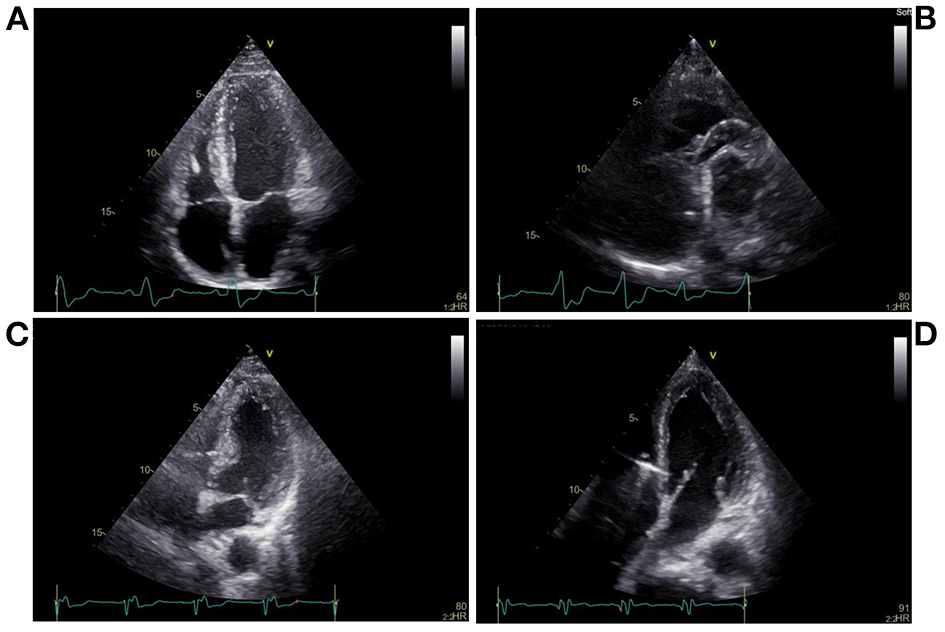

The pacing procedures were performed in a cardiac catheterization laboratory. Twelve-lead electrocardiogram (ECG) and intracardiac electrograms were simultaneously displayed and continuously recorded during all pacing interventions on a multichannel Bard Electrophysiology Lab System recorder (Bard, Haverhill, MA, USA). A catheter with a 6-Fr quadripolar electrode was inserted via the right external jugular vein; the electrodes were positioned within the right ventricular (RV) apex (RVA) and RV outflow tract (RVOT) (Figures 1A,B). For HBP, a preformed sheath (C315 HIS, Medtronic, Minneapolis, MN USA) was inserted via the right external jugular vein and placed in the region near the tricuspid valve septal leaflet. A Select Secure pacing lead (Model 3830, 69 cm, Medtronic) was delivered along the sheath with its distal part beyond the tip of the sheath for HBP recording (Figure 1C). For LBBP, the lead was twisted deeply through the ventricular septum from the RV septum to the endocardium of the LV septum to activate the LBB region (Figure 1D). According to the intracardiac electrograms, the LBB potential gradually appeared and increased as the electrode was screwed in, and the QRS morphology was gradually transformed from LBBB to RBBB. The interval between the LBB potential and ventricular activation was shorter than between the His bundle potential and ventricular activation. The imaging characteristics of LBBP showed that the pacing site was in the ventricular septum. The left or right anterior oblique projection was used to assist in identifying catheter positions; endocardial ECG was utilized to confirm these positions.

Figure 1

Echocardiography during pacing at different sites. (A) Right ventricular apical pacing, (B) Right ventricular outflow tract pacing, (C) His bundle pacing, (D) Left bundle branch pacing.